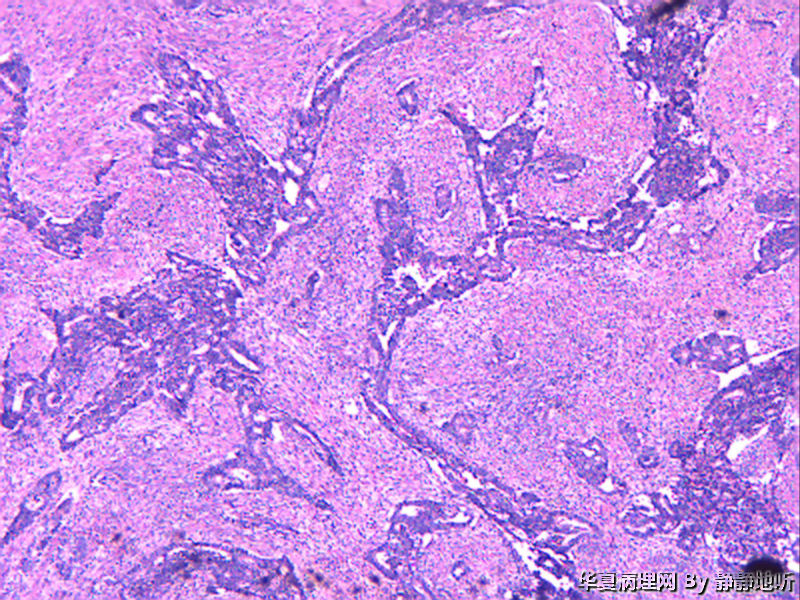

• 子宫肿瘤图3

图3

女性46岁,子宫峡部肿瘤,息肉样,体积3.5*4*3厘米,脱入宫颈,大体侵肌层。子宫肌壁明显增厚,大体似子宫腺肌症。

免疫组化:ck7-    CEA-    ER -   PR -   CD10 -   Vimentin -   ki-67 约60%